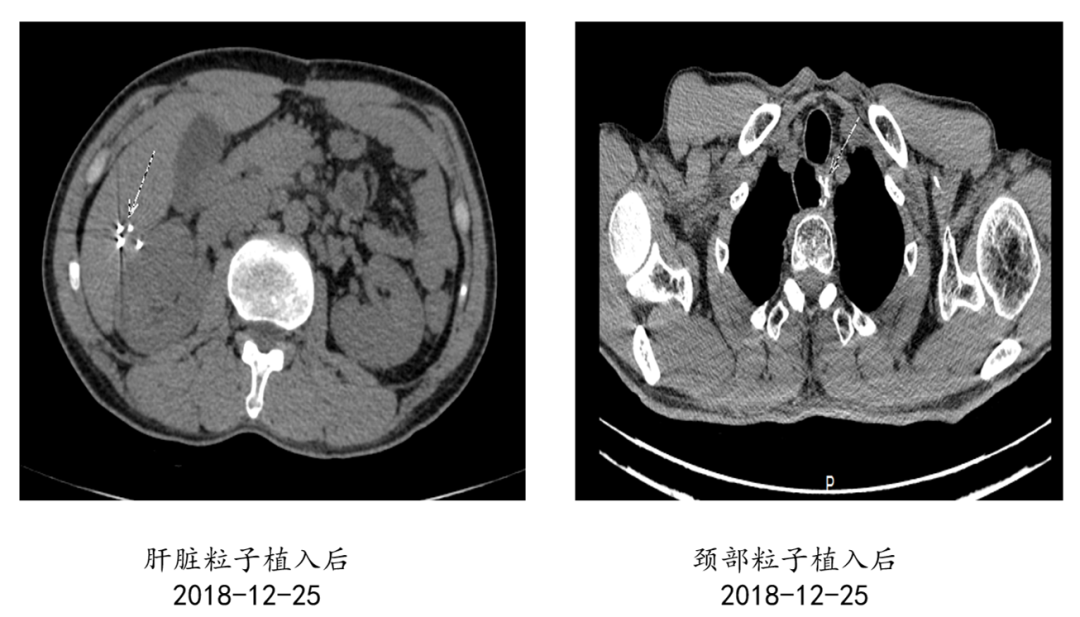

一个人生病时,回想这一生,什么对他来说最重要呢? 2020年,是马先生抗争病魔的第5个年头。 “我老公是15年12月份...